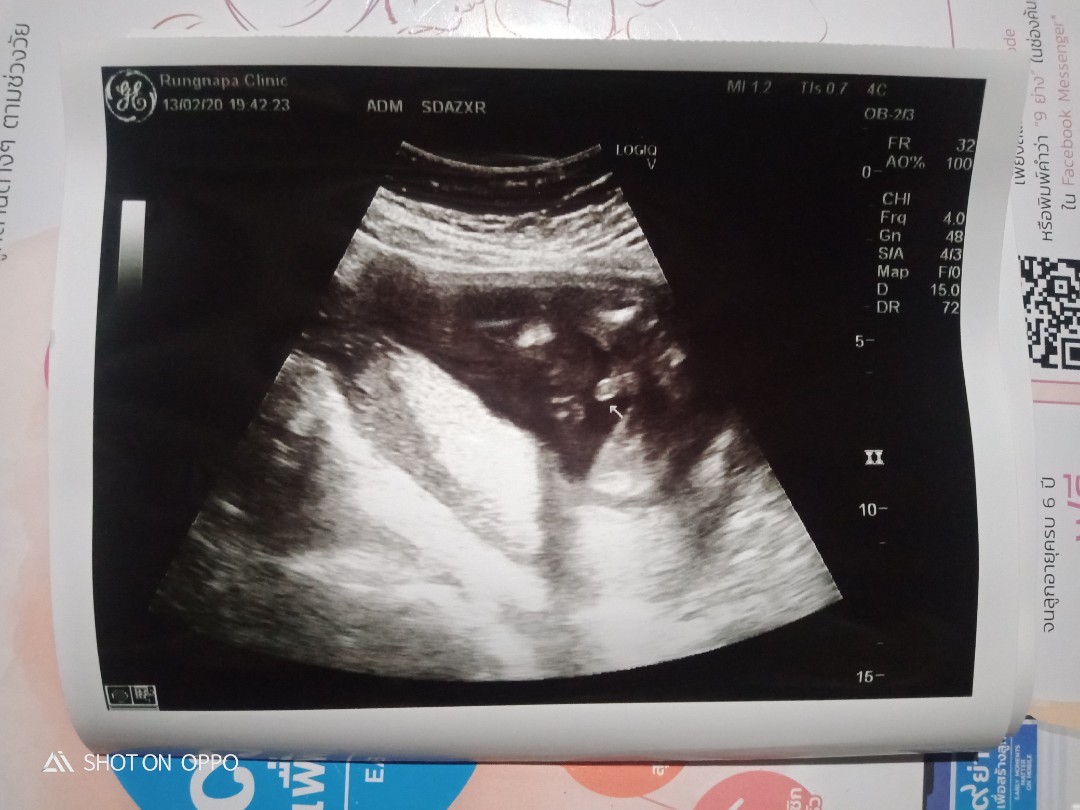

ผู้ชายค่ะ 31+5 วีค

ตรงลูกศรเลยค่ะ